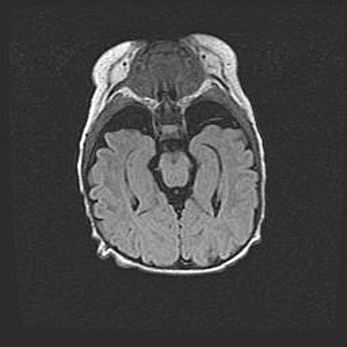

Множественные кисты обоих полушарий головного мозга, наибольшая из них в правой затылочной области. Ассиметричная атрофическая гидроцефалия.

Возраст: 7 месяцев

Вес: 5660 г

Пол: мужской

Окружность головы: 41,5 см

Срок гестации: 28-29 недель

Кисты головного мозга развиваются в результате многоочаговых некрозов вещества мозга и возникают вследствие перенесенной перинатальной инфекции, менингитов, энцефалитов, асфиксии, родовой травмы, расстройств мозгового кровообращения различного генеза. Образованию кист в веществе головного мозга плодов и новорожденных способствуют такие факторы, как высокое содержание в нем воды, недостаточная (или отсутствие) миелинизация и слабая астроглиальная реакция на повреждение.

Кисты могут сочетаться с гидроцефалией и другими поражениями головного мозга.